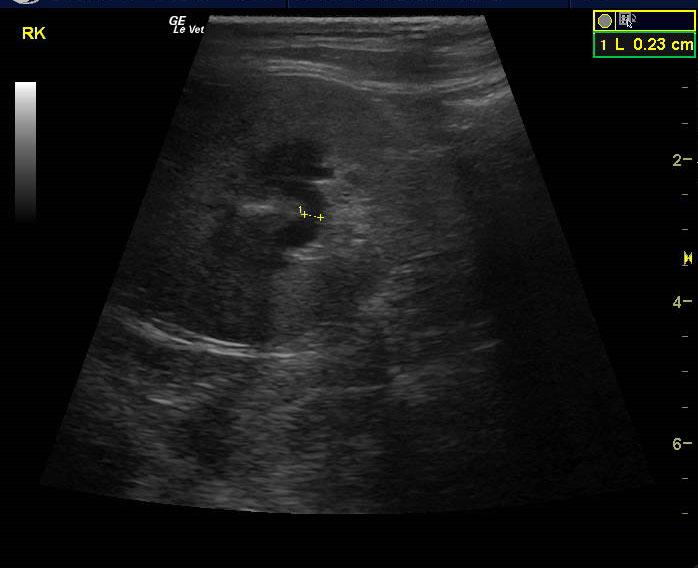

A 15 year old spayed female DMH cat was presented for progressive disease over a 6-8 month period, characterized by poor coat quality, decreased mobility, reduced activity, and pruritic skin lesions that have not responded to antibiotics and use of an E-collar. Abnormalities on physical examination were alopecia, hyperpigmentation, and thinning of the skin of the ventrum, and a non-healing, plaque-like, superficial skin lesion on the cranial aspect of the left stifle and accessory pad of the left carpus. Skin biopsies were scheduled. On urinalysis an inappropriate SG and proteinuria was present with a urine protein: creatinine ratio of 0.3. Abnormalities on serum biochemistry included hypercalcemia and hyperproteinemia. Radiographs showed arthritis of elbow, LS junction, and hips, as well as a mass in the region of the left kidney.